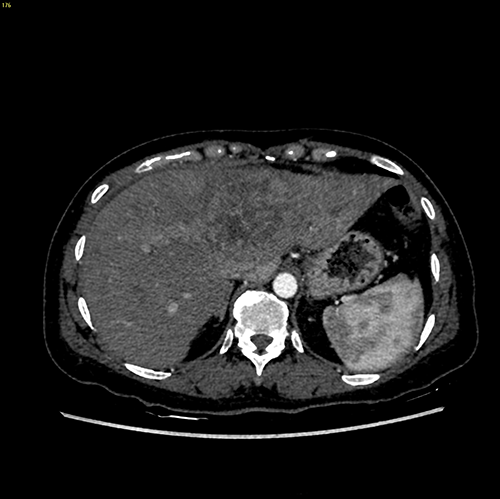

左肝巨大肝癌--左肝巨大肝癌切除